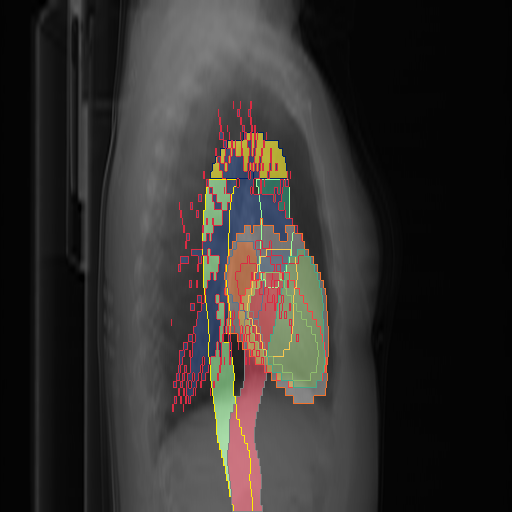

We show qualitative results for frontal projections in Fig. 2. We show a subset of classes belonging to the supercategories lungs, vascular systems, bones, and abdomen/digestive system. The predictions show minor deviations at the boundaries of the individual classes of the respiratory and vasculature system, while some inaccuracies become visible in the abdominal area. The qualitative results for the lateral projections are displayed in Fig. 2. Akin to the frontal view, the predictions show smoother borders but align with the ground truth. Apart from this, the segmentations provide matching insights on the thoracic anatomy with a slight deviation from the ground truth for both frontal and lateral views.

We display qualitative results in Fig. 3. The annotators tend to be content with most annotations. There are edits at the extensions of the esophagus, trachea, and aorta and corrections of the lower ribs. There is little consensus for classes in the abdominal area, such as the stomach, as seen on the right of Fig. 3 . In contrast, the annotators often align for bone classes.